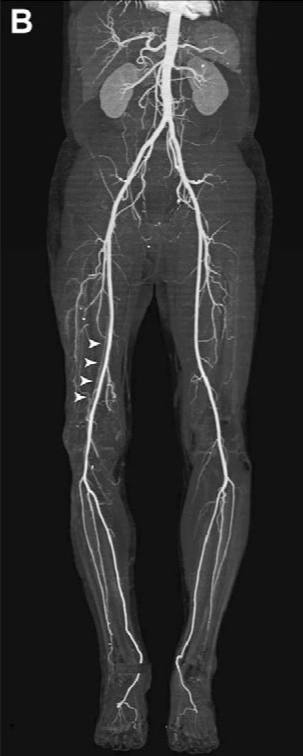

При цьому фахівець отримує об’єктивну інформацію про анатомічну будову судинного русла досліджуваної області, швидкості кровотоку, наявності стенозів (звужень) і оклюзій (повної закупорки), ступеня розвитку колатерального кровообігу в досліджуваній кінцівки.

При виконанні ангіографії фахівець отримує об’єктивну і точну інформацію про будову і ураженні артеріального русла досліджуваної області. Отримані зображення зберігаються в електронному вигляді і згодом можуть бути записані на диск і віддані на руки пацієнту.

Артеріографія нижніх і верхніх кінцівок - при діагностиці облітеруючих захворюваннях артерій (облітеруючий атеросклероз, ендартеріїт).

Це метод візуалізації просвіту артерій та вен шляхом введення в них через катетер рентгеноконтрастних речовин і одночасної рентгеноскопії (відеозапису рентгенівської зйомки), з фіксацією і обробкою отриманого зображення на спеціальному обладнанні.